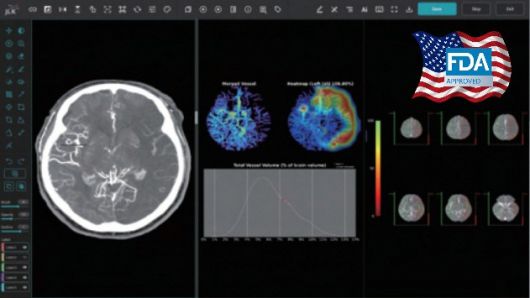

이를 보완할 수 있는 것이 제이엘케이의 뇌졸중 대혈관폐색 솔루션(JLK-LVO)을 비롯한 뇌졸중 검출 기술이다. JLK-LVO는 CT 뇌혈관 영상을 분석해 의료진이 수술 필요성을 신속하게 결정할 수 있도록 한다. 제이엘케이는 뇌졸중 관련 AI 솔루션 13종과 함께 의료용 앱 스냅피 또한 보유했다. 스냅피는 응급의학과, 신경과, 신경외과 등 의료진 간 AI 분석 결과를 공유하고 실시간 대화로 빠른 협진을 돕는다. 의료 취약지 내 뇌졸중 환자 상태를 이송 도중에 확인하고 시술 계획을 빠르게 수립할 수 있어 치료까지 소요되는 시간도 대폭 줄일 수 있다.